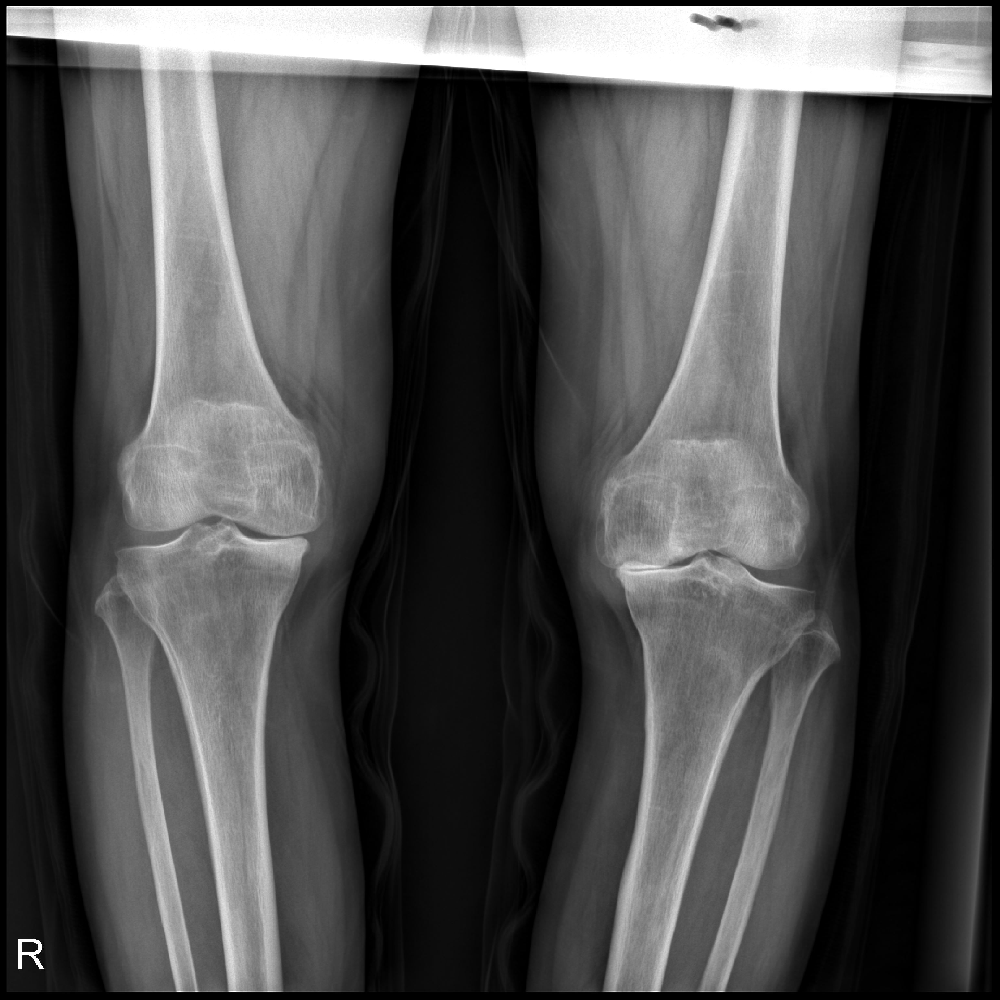

馬廣娥,現(xiàn)年68歲,是嶧城區(qū)峨山鎮(zhèn)趙莊村后山頭村的一位普通老人,卻有著不平凡的人生經(jīng)歷。10年前,她的雙膝關(guān)節(jié)開始出現(xiàn)持續(xù)的疼痛,讓她苦不堪言。試想一下,當(dāng)年風(fēng)華正茂的馬廣娥是否想到,她將從此以后背負(fù)著這樣一道無盡的痛苦?

見識醫(yī)生,接受治療,似是唯一的出路??上?,時間的推移并沒有給馬廣娥帶來明顯的好轉(zhuǎn)。兩年來,疼痛反復(fù)交替出現(xiàn),甚至逐漸導(dǎo)致了她雙膝內(nèi)翻的畸形。馬廣娥的人生就像一首哀婉的曲子,曲調(diào)悲切,令人感嘆不已。

然而,在黑暗中總有一束光明,讓人堅定地朝著光明前進(jìn)。在馬廣娥苦苦掙扎的時刻,她被送往市中區(qū)誠德骨科醫(yī)院接受細(xì)致入微的檢查和治療。終于,醫(yī)生決定為她進(jìn)行雙膝關(guān)節(jié)內(nèi)側(cè)活動平臺單髁置換術(shù),這一手術(shù)將為她帶來翻天覆地的改變。

圖片1.png